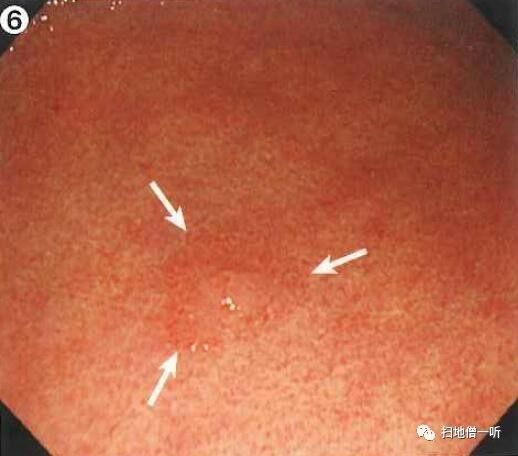

背景粘膜为C-2型萎缩。体部淡红色弥漫发红提示HP感染。体下部大弯侧可见小片褪色斑,周围未见相同表现病灶。

接近观察可见褪色斑边界较清晰

靛胭脂染色后可见HP感染的周围胃小区大小不等,与病灶处胃小区未见明显差别,表面凸凹不明显,怀疑印戒细胞癌